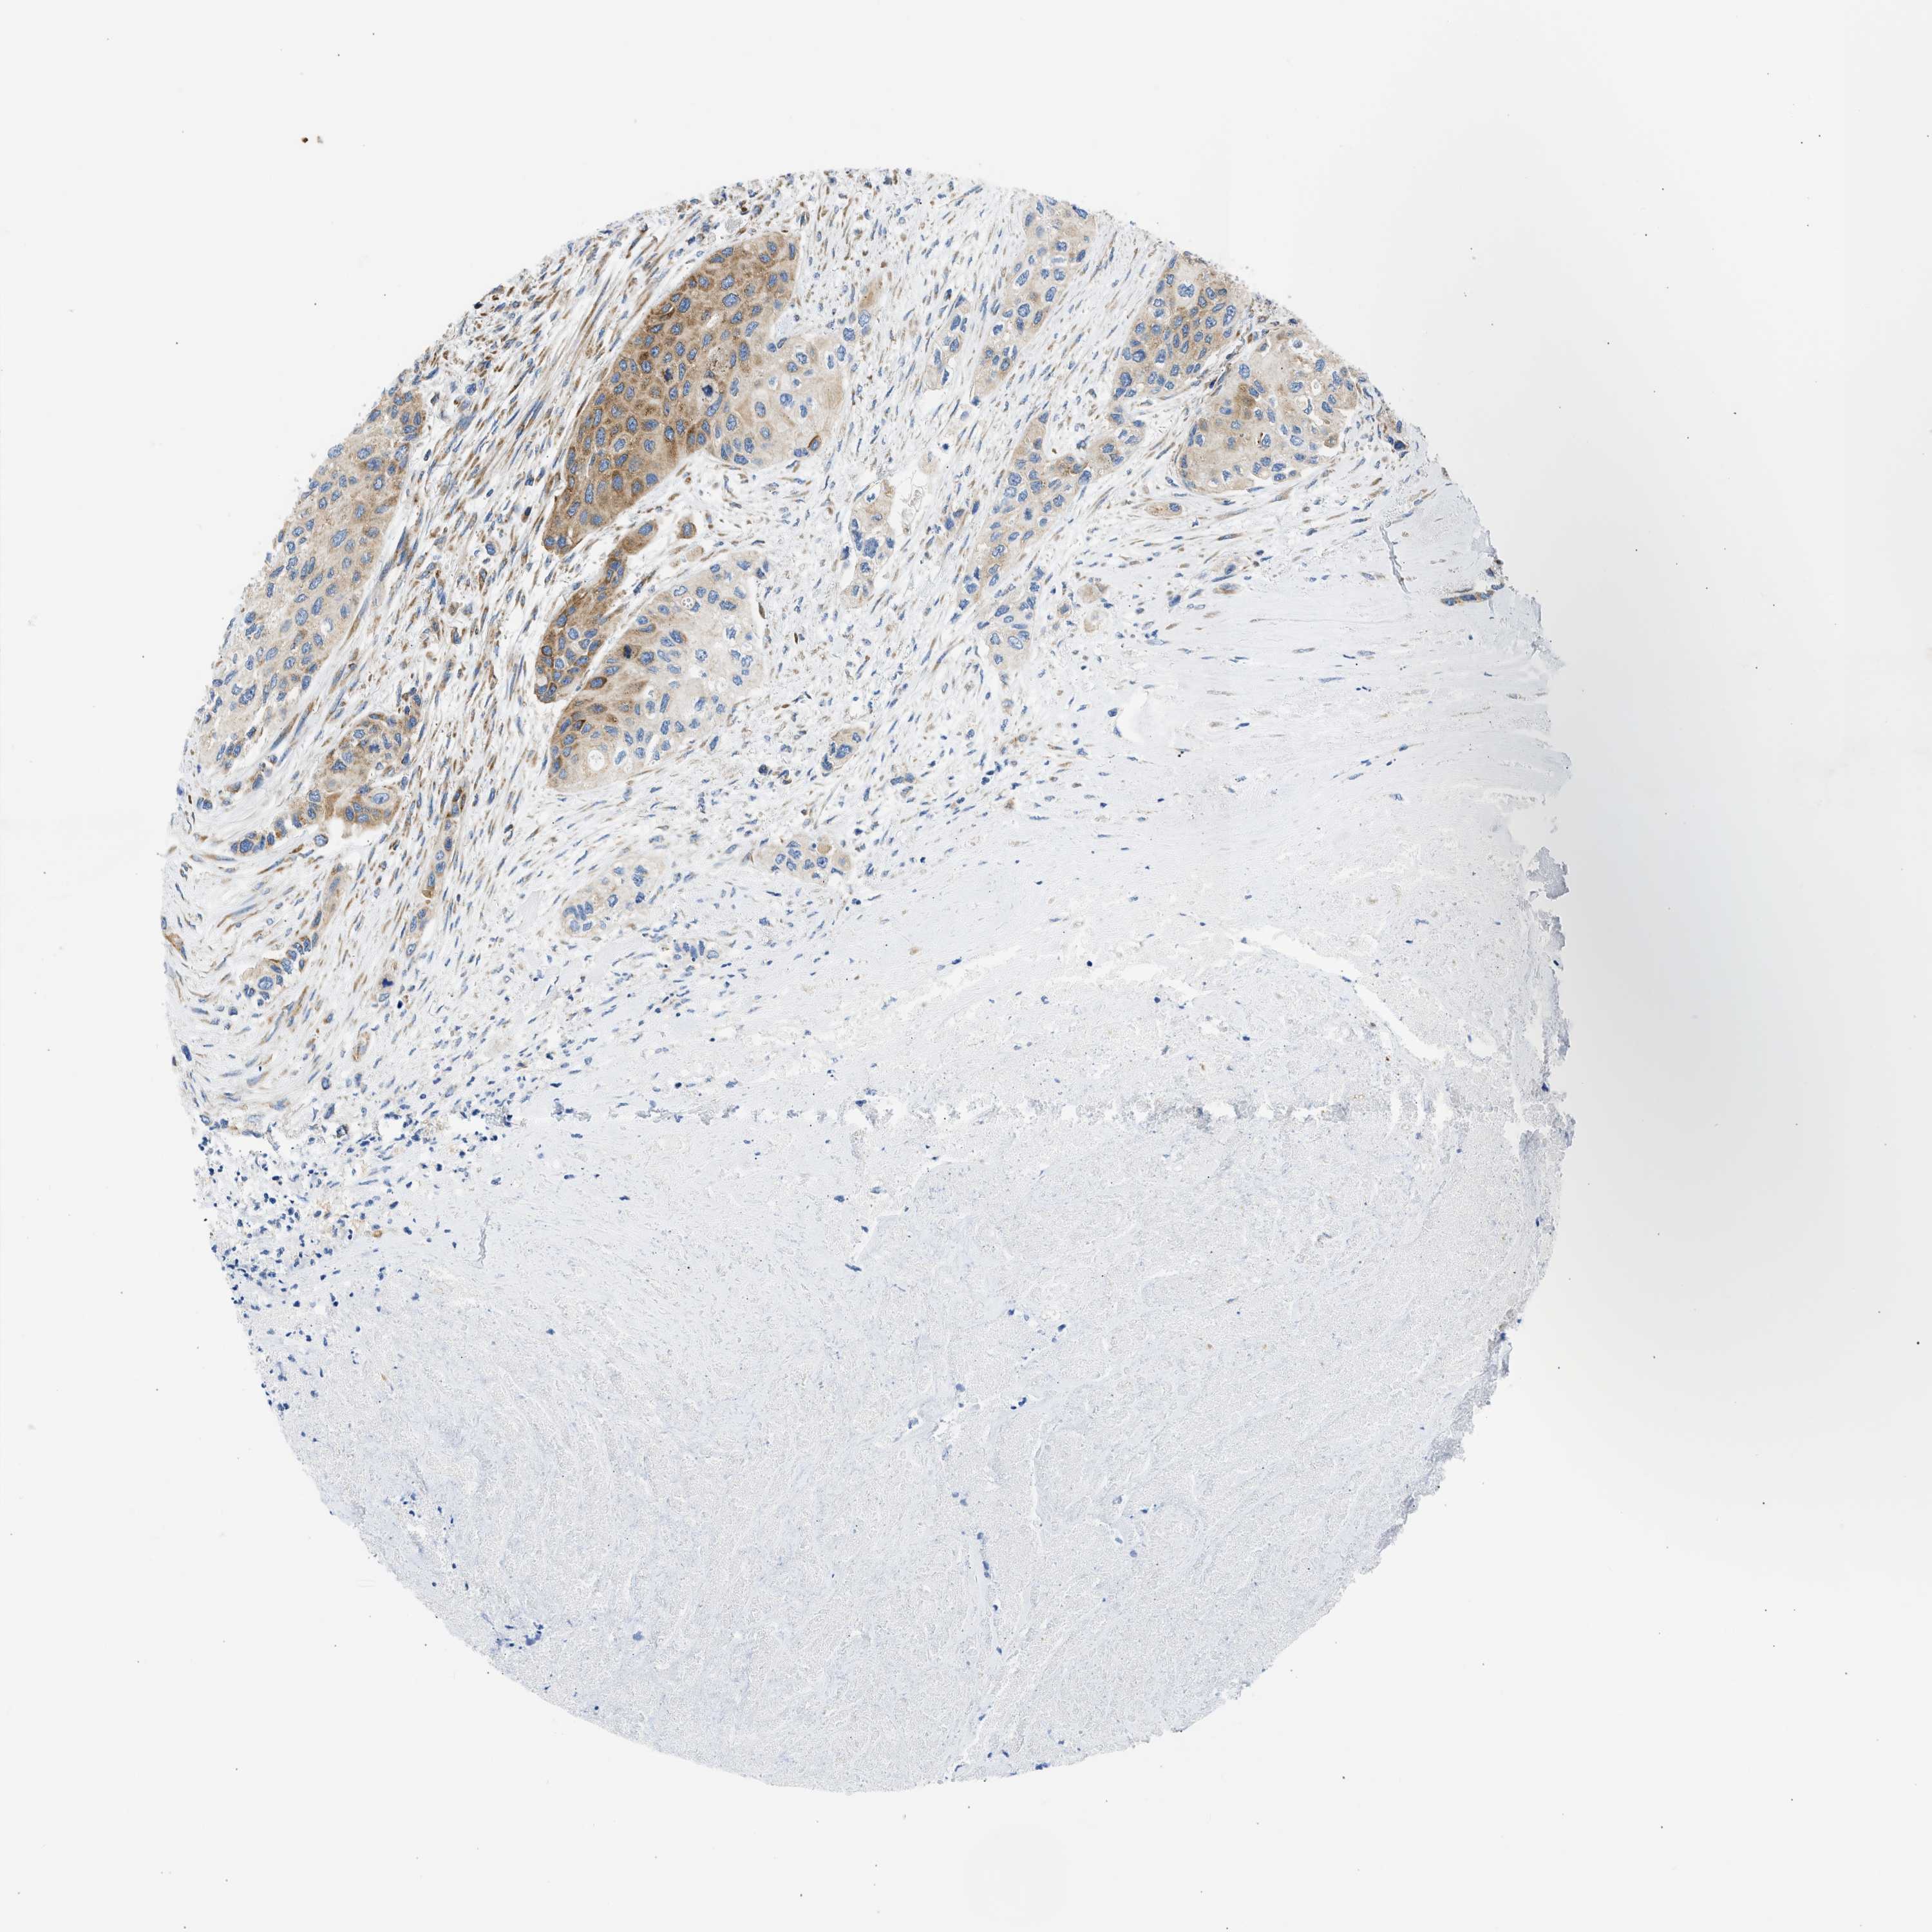

UROTHELIAL CANCER - Protein expressioni

A mouse-over function shows sample information and annotation data. Click on an image to view it in a full screen mode. Samples can be filtered based on level of antibody staining by selecting one or several of the following categories: high, medium, low and not detected. The assay and annotation is described here.

Antibody stainingi

Antibody staining in the annotated cell types in the current human tissue is reported as not detected, low, medium, or high, based on conventional immunohistochemistry profiling in selected tissues. This score is based on the combination of the staining intensity and fraction of stained cells.

Each image is clickable and will lead to virtual microscopy that enables deeper exploration of all samples and also displays staining intensity scores, fraction scores and subcellular localization as well as patient and tissue information for each sample.

Antibody HPA017389

Antibody HPA063713

Staining

High

Medium

Low

Not detected

Intensity

Strong

Moderate

Weak

Negative

Quantity

>75%

75%-25%

<25%

None

Location

Nuclear

Cytoplasmic/membranous

Cytoplasmic/membranous,nuclear

Urothelial carcinoma, Low grade

Urothelial carcinoma, High grade

Urothelial carcinoma, NOS